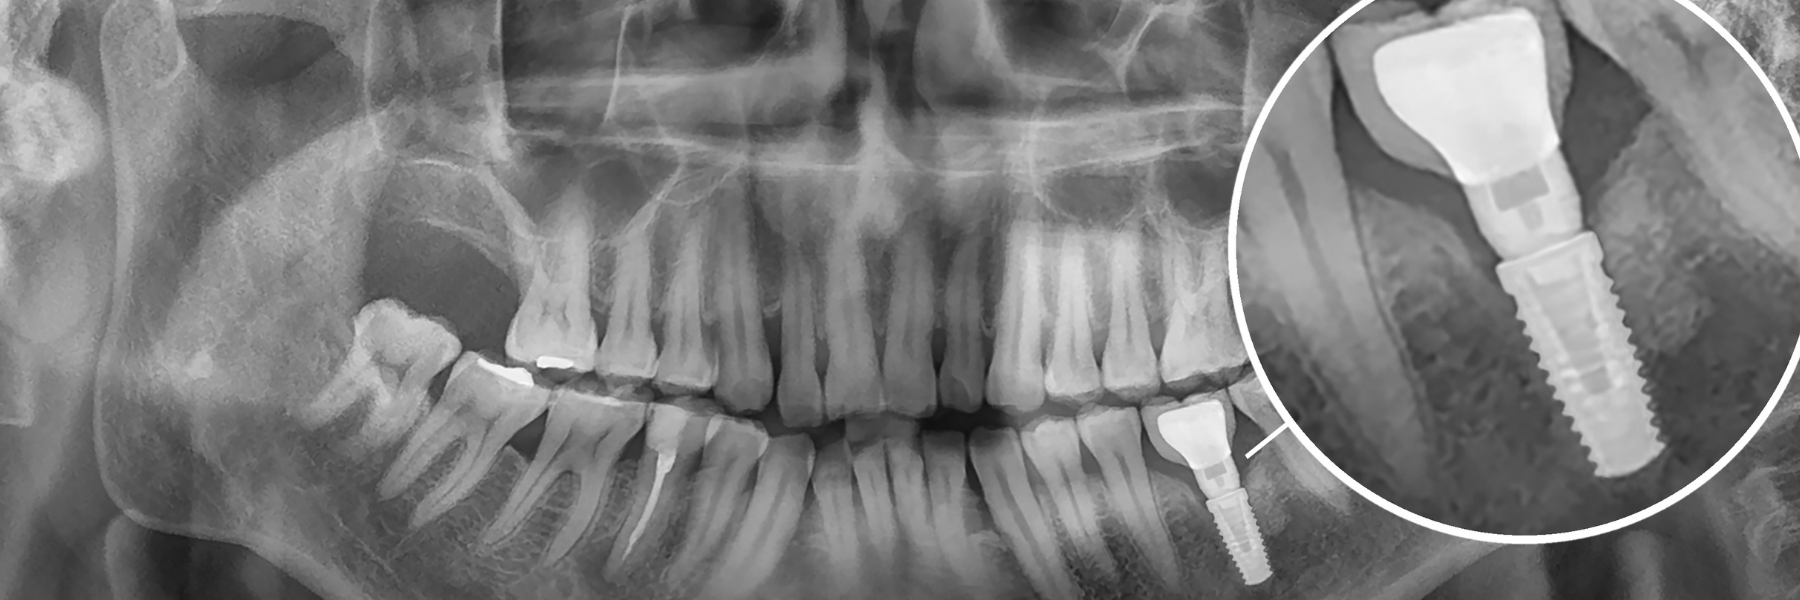

Dental implants are now considered the gold standard in tooth replacement. It is the only system available that replaces both your tooth and its valuable root.

When you replace your tooth’s root, it may help prevent jawbone deterioration, which is a common problem associated with tooth loss. Your implant may stimulate this bone to keep it viable.

The healing process is an important step in the dental implant procedure so that the implant can support the load from chewing. During this integration process, your jaw bone will grow into the threads of the implant and secure it firmly in place.

Step Four – Dental Implant Crown

Once it has been confirmed that your implant has integrated fully and the surrounding bone is healthy, you will return for the final stage, which is securing a new crown over the implant. The crown replaces your tooth and restores the chewing surface. Each crown is a custom-designed restoration to fit and function like a natural tooth. The final step actually takes place over 2 appointments. At the first appointment, we will take another 3D scan of your jaw, this time with the implant as a reference point so our laboratory technician can fabricate the perfect crown for you. Approximately 3 weeks after the scan, you return for your final visit to have your tooth placed. The crown is always tried in first before being secured permanently. Once we're all happy with the final result, the crown is then secured over the implant.